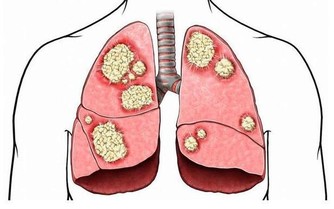

4.性早熟是個禍害

性早熟會導致孩子骨齡超前,雖然短時間內他們會比其他孩子高,

但是發育結束後,他們的最終身高會達不到平均標準。

所以當孩子有性早熟情況的時候,一定要找醫生。

平常家長不要讓孩子過早接觸不健康的信息,拒絕不健康的食品,減少激素的攝入。